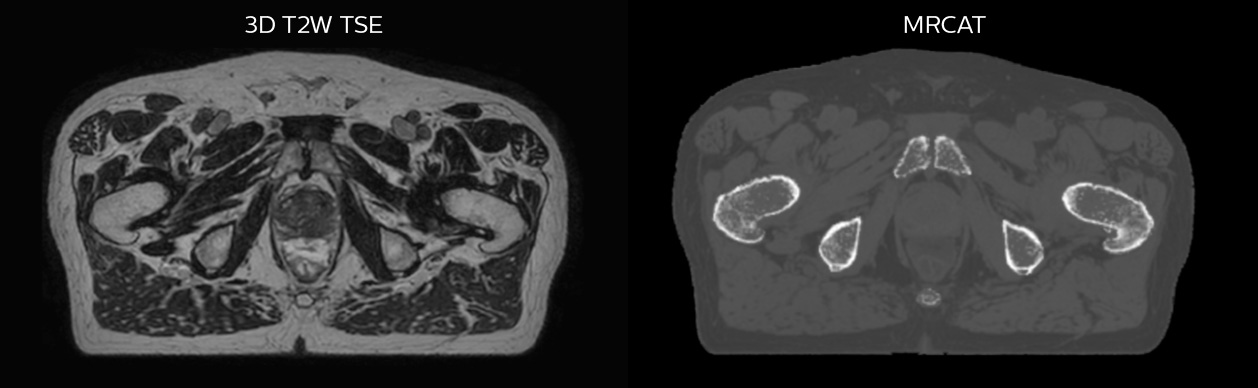

MR-only radiotherapy planning with MRCAT

Philips MRCAT (MR for Calculating ATtenuation) provides exceptional soft tissue contrast for target and OAR delineation, in addition to the Hounsfield units needed for dose calculations. This permits an MR-only radiotherapy planning workflow. Philips pioneered MR-only radiotherapy with the introduction of MRCAT Prostate, followed by the expansion to the whole pelvis with MRCAT Pelvis. This application can be used for a broad range of pelvic indications, including cancers in the prostate, rectum, bladder, anal canal and cervix. Next to MRCAT Pelvis, MRCAT Brain is available for radiotherapy planning of primary and metastatic soft-tissue tumors in the brain.

Hôpital de La Tour uses an implanted rectal spacer (SpaceOAR®, Boston Scientific) for patients receiving prostate radiotherapy to provide space between the rectum and prostate. 3D T2W TSE MRI provides excellent rectal spacer visualization and is used for OAR and target contouring. The dose plan is calculated on the MRCAT dataset.

Simulation imaging

Tranversal 3D T2W TSE with Compressed SENSE, acquired on Ingenia MR-RT 1.5T (left).

On-console generated MRCAT (right).

MR-based contouring and planning

MRCAT is primary image dataset for dose calculation (left).

3D T2W TSE MRI with 36 cm Field-of-View is used for delineation of prostate and organs at risk (right).